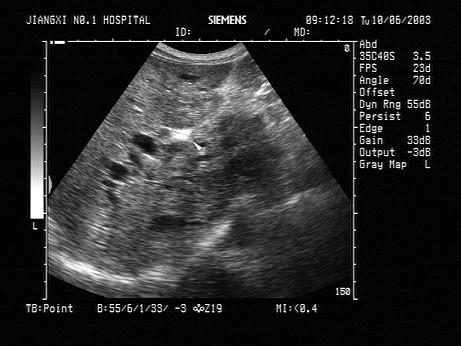

问题 男,47岁,上腹部疼痛不适、腹胀,皮肤巩膜黄疸,进行性加重,皮肤搔痒。声像图如图所示,最可能的诊断为?(?)

选项 A.肝癌 B.肝门部淋巴结肿大 C.肝门部胆管癌 D.肝门部胆管胆汁淤积 E.肝门部转移性癌

答案 C